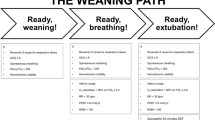

To date, no weaning predictive index has proven to be ideal [1]. According to the Sixth International Consensus Conference on Intensive Care Medicine [2], patients who meet the following satisfactory criteria should be considered ready for weaning: frequency to tidal volume ratio (f/Vt) less than 105 breaths/min/L, respiratory rate (f) of 35 breaths/min or less, maximal inspiratory pressure (MIP) of -20 or less to -25 cmH2O, tidal volume (Vt) more than 5 mL/kg, vital capacity more than 10 mL/kg, and arterial oxygen saturation (SaO2) above 90% with a fraction of inspired oxygen (FiO2) of 0.4 or less (or partial pressure of arterial oxygen (PaO2)/FiO2 ratio of 150 mmHg or above). After the assessment of these indexes regarding readiness for weaning, a spontaneous breathing trial (SBT) should follow as a diagnostic test to determine the likelihood of successful extubation [3].

Three hundred and thirty-one patients who were on mechanical ventilation for more than 24 hours were evaluated. Patients younger than 18 years of age or with neurological and neuromuscular diseases were excluded from the study. The study was conducted from September 2004 to January 2008 in three general intensive care units (ICUs) of the Hospital de Clínicas de Niterói (Rio de Janeiro - Brazil), totaling 27 beds. It was approved by the ethics committees of our institution and registered as an International Standard Randomized Controlled Trial under number 92117906. Informed consent was obtained from each patient, whenever possible, or from the patient's next of kin. The ventilators used were Evita 2 (Dräger, Lübeck, Germany). Discontinuation from mechanical ventilation was attempted when the physician in charge judged that the patient was ready to be weaned, according to the following criteria: the cause for starting mechanical ventilation had resolved or at least improved; body temperature was below 38.5°C; hemoglobin was equal to or higher than 8 g/dl; and none or a minimal dose of vasoactive or sedative drugs was administered. A PaO2 of 60 mm Hg or more or SaO2 of 90% or more with a FiO2 of 0.4 or less and positive end-expiratory pressure (PEEP) of 8 cmH2O or less were other criteria to be met. A SBT was then evaluated by means of a 2-hour T-piece.

Weaning was considered successful if spontaneous breathing was sustained for more than 48 hours after extubation [2]. During the two-hour period of SBT, tolerance was continuously evaluated by the physician in charge. When the patient remained stable after the two-hour period of SBT, the endotracheal tube was removed. The trial was stopped when at least one of the following poor tolerance criteria was present: SaO2 less than 90% and PaO2 less than 60 mmHg with FiO2 less than 0.5 or SaO2 less than 88% and PaO2 less than 55 mmHg with FiO2 less than 0.5 in patients with chronic obstructive pulmonary disease (COPD); partial pressure of arterial carbon dioxide (PaCO2) more than 50 mmHg (or increased by 8 mmHg or more in COPD patients); arterial pH of 7.33 or less or decreased by 0.07 or more; f more than 38 breaths per minute or increased by 50% for five minutes or longer; heart rate of more than 140 beats per minute or a sustained increase or decrease in more than 20%; systolic blood pressure of more than 180 mmHg or less than 90 mmHg; or in the presence of agitation, diaphoresis, disorientation or depressed mental status. A clearly audible cough and adequate mental status were requirements for patients to be considered ready for extubation [15].

In training set, the threshold values of each index that best discriminate between successful or unsuccessful weaning were: PaO2/FiO2 ratio of 255 or more; Cst,rs of 30 ml/cmH2O or more; IWI of 25 ml/cmH2O breaths/minute/liter or more; P 0.1 of 3.1 cmH2O or less; f of 30 breaths/minute or less; Vt of 315 ml or more; f/Vt ratio of 100 breaths/minute/liter or less; and P 0.1 × f/Vt ratio of 270 cm H2O/min/liter or less.